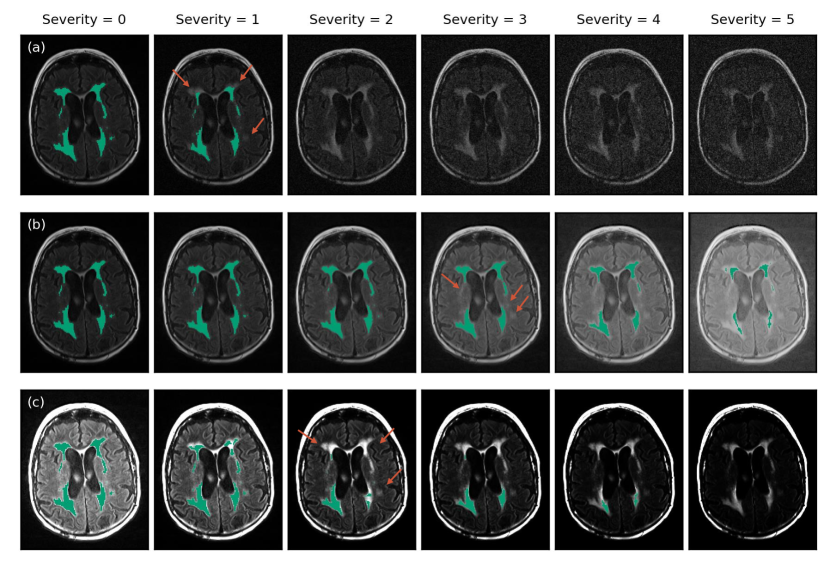

Refer to caption

Figure 3: Transform severity levels with increasing severity from left (severity == 0; no transform applied) to right (severity == 5; maximum level applied). Examples are shown for the (a) ghosting (motion artifact), (b) isotropic downsampling, and (c) MRI noise transforms. The images shown are taken from a T1 volume sliced axially through the hippocampus.

Following the approach of Hendrycks and Dietterich [2019], we defined five distinct severity levels for each transform (see Figure 3). Severity levels capture various magnitudes of distribution shifts, from mild to severe. Ideally, the chosen severity levels would span the range of distribution shifts seen in practice across imaging sites. However, there is a lack of quantitative studies investigating these ranges in the field, and it is not straightforward to translate observed variances into parametrically-modeled transforms. Thus, severity levels were chosen based on extensive visualization to fit in line with mild and extreme cases from the authors’ experience with multi-site studies, and corruptions observed in practice (e.g., due to poor quality, artifacts or patient movement). To properly model severity levels and corruptions, scans with artifacts were removed or corrected in our clean test set prior to transformation. These severity levels may need to be re-optimized or calibrated if applied to other applications/tasks where the dataset characteristics differ drastically from those used in this study. For transform parameterizations corresponding to each severity level, see Supplementary Table S1.